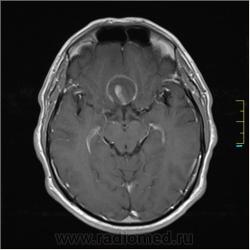

Пациентка направлена на исследование с диагнозом "Гипертонический криз"

Пациентка направлена на исследование с диагнозом "Гипертонический криз", энцефалопатия неуточненная.

частично функционирующая аневризма

Иначе говоря, аневризма с хронической геморрагией, т.к. мы видим фракции крови различного возраста.

По-моему, аневризма с пристеночными тромбами.

Постепенное пристеночное образование тромбов приводит к появлению типичного для аневризмы феномена -слоистости МР сигнала в полости аневризмы. Данная картина демонстрирует слоистый характер тромботических масс в полости аневризмы .Функционрирующая часть имеет низкий сигнал во всех режимах сканирования. Дополнительно-перифокальный отек.

А может более корректно интерпретировать как частично тромбированная аневризма... Уж коь речь идет о фракциях, ну то есть о тромбе по сути.... Ну и плюс перфокальный отек головного мозга (вероятнее цитотоксический+вазогенный).